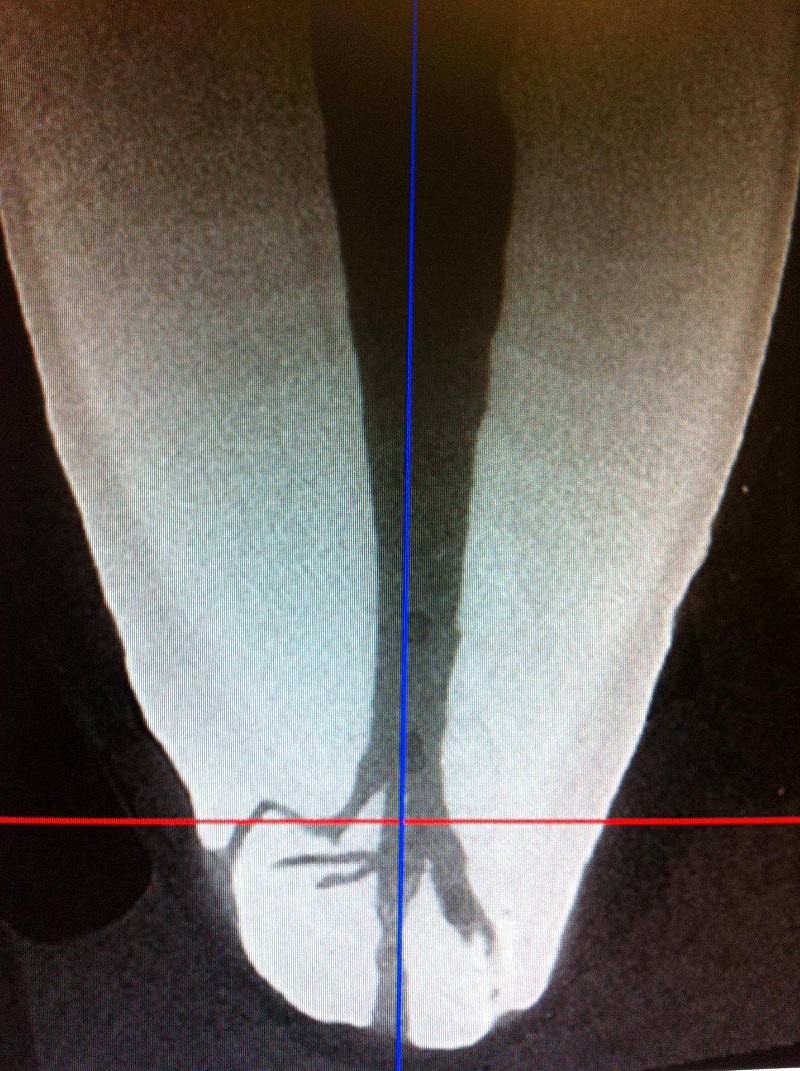

If you are concerned a root canal may be effecting your health, going to your local dentist to get it removed would be a waste of time. You would probably be better off just leaving it in. The reason is because most dentists don't remove the infected bone around a tooth. In the case of a root canal, the bone must be aggressively cleaned to make sure all the infection is gone. It also must be done in a way that won't damage the bone. Drilling away bone can overheat and kill it, implant surgeons know this well. The bone should be cut away with hand tools if possible, or drilled using a low speed drill cooled with saline. Ozone can be used to kill the anaerobic bacteria that will inevitably be present. The bone will grow over the top of the site where the root canal site was, regardless as to whether the bone was surgically cleaned out or not. If it wasn't, you will be left with a pocket of infection inside the bone, which might be just as bad, or worse for your health. This is my surgery picture of the infected bone being removed around where my root canal tooth used to be. Yes sadly it was a front tooth.